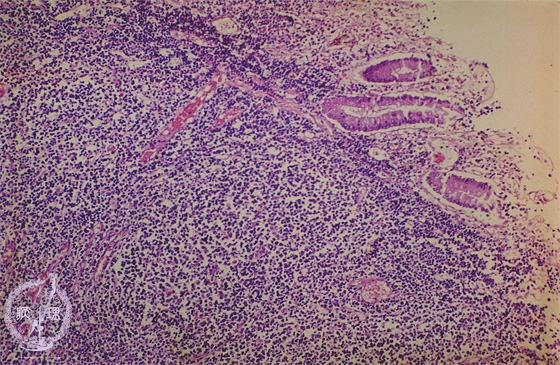

- ★(9)Malignant lymphoma of the stomach (MALT lymphoma)

Microscopic view (H&E stain, intermediate power): The mucosa is displaced due to proliferation of atypical lymphocytes.